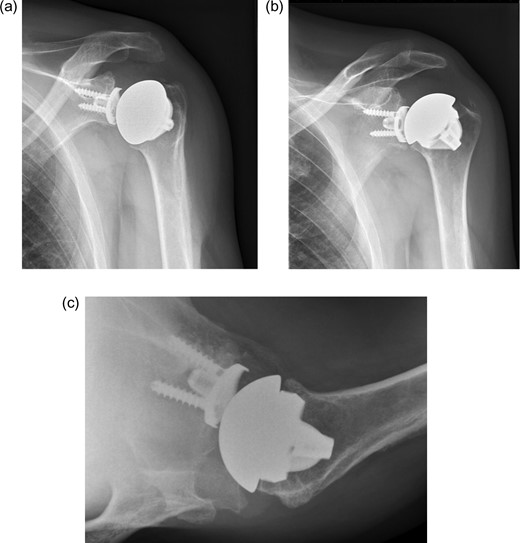

The first case is a 50-year-old man who works as a butcher. He has alkaptonuria, which was confirmed in a biopsy taken at a knee arthroscopy in 2010. He reports pain in his left shoulder. Physical examination shows an active and passively restricted range of motion. Radiological examination (Figure 1) shows glenohumeral osteoarthritis of the left shoulder. MRI shows an intact rotator cuff with signs of tendinopathy. A stemless cementless total shoulder arthroplasty was implanted (Shoulder Modular Replacement (SMR) Stemless, LIMA) (Figure 2). During surgery, the rotator cuff was intact. One year after implantation patient was satisfied regarding pain and functioning, radiography did not show any signs of loosening or other complications.

X-ray of left shoulder with total shoulder arthroplasty one year post-operative. (a) AP external rotation view. (b) AP internal rotation view. (c) Axial view.